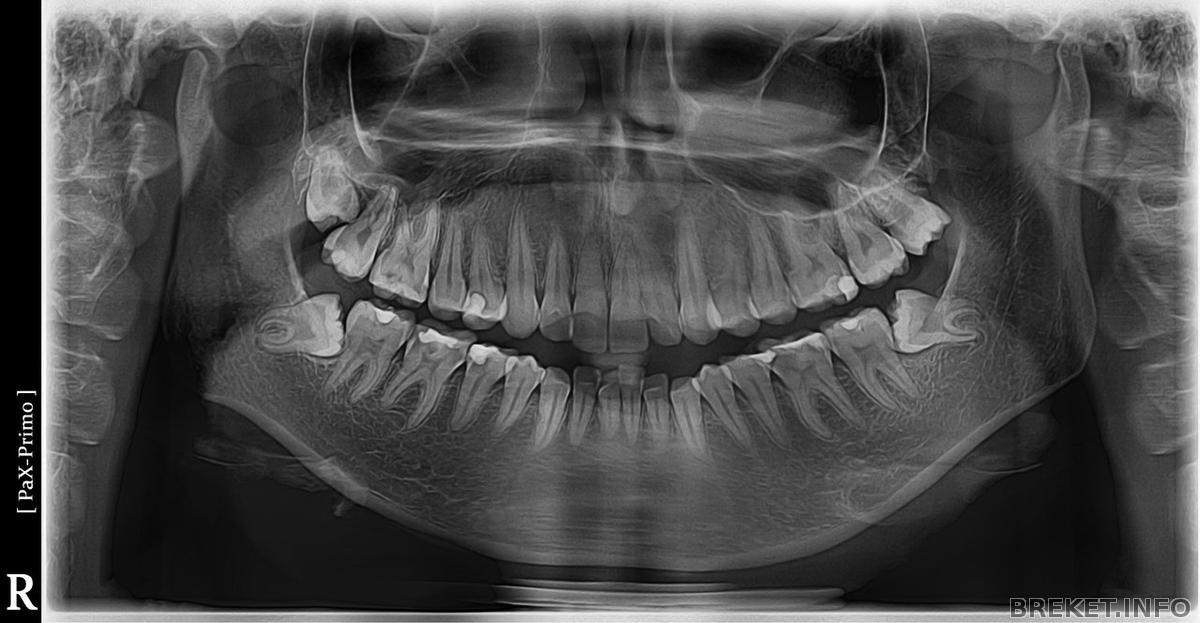

Первый шаг к красивой улыбке:)

Панорамный

Панорамный снимок

снимок.